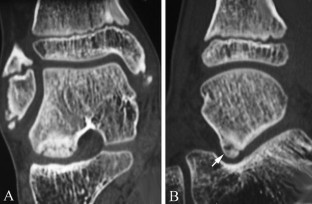

Osteochondritis dissecans of the talus is classically characterized by an abnormality of the articular cartilage of the talar dome. We report a rare case of a lesion of the subtalar facet in a 10-year-old boy. The lesion was responsible for a painful ankle with secondary instability. The diagnosis was made using plain radiographs and CT, which showed a well-circumscribed osteochondral fragment demarcated from the adjacent bone by a radiolucent line. The clinical outcome was favourable after a 6-week period with a non-weight-bearing short-leg cast.

Fig. 1